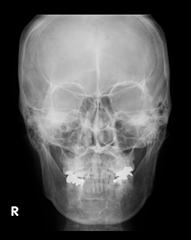

一般撮影検査

X線撮影とは、一般的に「レントゲン撮影」と呼ばれている検査です。

X線を人体に照射し、透過したX線をフラットパネルディテクタを使って画像化することで、人体内部の情報が得られます。

一般撮影は、わずかなX線で撮影が可能であり、撮影も短時間で施行できます。

当院では、胸部・腹部・骨格系の撮影・造影剤を用いた尿路系撮影などの検査を行っています。